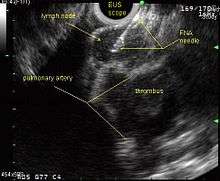

A metaanalysis published in 2007, based on 1,201 cancers in 18 high-quality clinical trials carefully selected by predefined criteria from the literature, systematically examined the performance of EUS-guided FNA in NSCLC staging. Two scenarios were considered: the setting of enlarged lymph nodes on CT (suggestive but not diagnostic of cancer), and the obverse scenario of an absence of lymph node enlargement on CT (suggestive but not diagnostic of no cancer).[24] Overall, in both settings, minor complications were reported in 0.8% of procedures; no major complications were recorded. EUS-FNA in enlarged discrete mediastinal lymph nodes had an excellent pooled sensitivity (8 studies) of 90% (95% CI, 84 to 94%) and specificity of 97% (95% CI, 95 to 98%). EUS-FNA in the setting of no enlarged mediastinal lymph nodes on CT had a pooled sensitivity (4 studies) of 58% (95% CI, 39 to 75%) and specificity of 98% (95% CI, 96 to 99%). Although this sensitivity (58% in CT-negative disease) might on first consideration seem disappointing, if EUS is performed as a staging test it can help avoid more invasive staging procedures, or surgery, if positive (for the presence of cancer). In other words, an EUS that has a positive result (shows cancer) will avoid further needless surgery, whereas a result not showing cancer may be false-negative, and probably requires an excisional biopsy technique for confirmation, such as VATS or mediastinoscopy.

The ACCP guidelines recommend invasive staging for patients with or without mediastinal lymph node enlargement on CT regardless of the PET scan findings. If needle techniques are used (such as EUS-NA, TBNA, EBUS-NA, or TTNA) a non-malignant result should be further confirmed by mediastinoscopy as explained above.